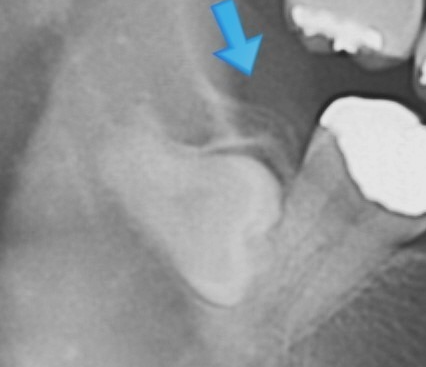

사랑니 발치는 일반 치아와 달리 신경과 가까이 있어 신경 손상 가능성이 있습니다. 하지만, 사랑니 발치를 해야 하는 경우 위험 부담이 있더라도 사랑니를 빼게 됩니다. 제3대구치라고도 불리는 사랑니는 어금니 맨 끝 쪽에 위치하고 있고 맹출 시기는 보통 17~21세 사이로 알려져 있습니다.

구강 내 모든 치열이 완성되고 뒤늦게 자라나는 사랑니는 제대로 맹출 되는 사람도 있지만, 옆으로 누워서 나거나 매복 상태로 통증만 지속되는 경우가 많습니다. 사랑니의 맹출 상태, 관리 방법에 따라 영구치로 유지하는 경우와 발치해야 하는 경우로 나뉩니다.

사랑니 발치 비용은 난이도에 따라 비용이 달라지며 매복이 심한 경우 발치가 불가능하기도 합니다. 난도가 높은 사랑니 발치 시 CT 장비를 갖춘 병원급 or 대학병원에서 발치하길 권장합니다. 사랑니 발치는 무조건 해야 하는 것은 아니며, 제대로 맹출 되었다면 제3대구치로 사용이 가능합니다.